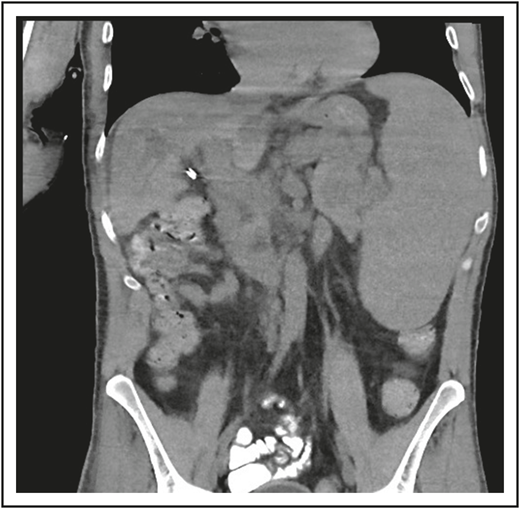

A third common reason for hematologists to see patients with CVID is a suspicion of lymphoma. Patient 3 is now a 47-year-old computer executive who came for a second opinion to the immunology department. He had had numerous sinopulmonary infections in childhood and then 2 episodes of shingles in his 30s. At the age of 36, he had acute AIHA treated with steroids. He then had an episode of cellulitis, and, with this, serum immunoglobulins were tested, which showed quite low levels: IgG, 186 mg/dL; IgA, 9 mg/dL; and IgM, 24 mg/dL. At the same time, his spleen was quite large. He was diagnosed with CVID, and immunoglobulin therapy was initiated. Owing to the enlarged spleen, now at 19 cm, a bone marrow biopsy was performed, and he was ultimately seen at another center at the age of 42, when the diagnosis of marginal zone lymphoma was made on the basis of bone marrow findings. He was treated with 6 cycles of rituximab and bendamustine. However, his splenomegaly persisted, and 3 years later, he sought an opinion at another medical center, where he was told that he did not have lymphoma on the basis of National Cancer Institute review of his bone marrow. Now, 5 years later, he has been well while receiving intravenous immunoglobulin, but he continues to have an enlarged spleen. There are no signs of lymphoma (Figure 3).

The patient in clinical case 3 was concerned because after he received chemotherapy for a presumed lymphoma, his spleen remained large. However, this is typical in patients with CVID.

Although lymphomas do occur in CVID, it must be emphasized that careful distinction between malignant and nonmalignant lymphoid proliferation in CVID is not simple, and as pointed out previously, clonal expansions occur in nonmalignant nodes, tissues, and blood in patients with CVID.24,25 When lymphomas do appear in CVID, they can be extranodal, usually B cell in type, EBV negative, and more common in subjects in the 4th to 7th decades of life. Lymphomas in CVID are not usually diagnosed by bone marrow biopsy; positron emission tomographic scans in CVID often demonstrate splenic enlargement and known lymphoid hyperactivity but may help point to a site for biopsy. A number of cases of marginal zone (MALT) lymphomas have been reported,26 in some cases related to Helicobacter pylori. Lymphoma may be more likely to arise in subjects with preexisting polyclonal lymphoproliferation, as shown for 10 cases in 334 subjects with CVID extracted from the ESID Registry. In this study, a higher baseline serum IgM in CVID was correlated with both lymphoid hyperplasia and lymphoma.10 These data were also confirmed in a US cohort of 476 subjects with CVID.3 However, as shown in clinical case 3, although lymphoid malignancies are increased in CVID, the diagnosis requires careful review. Potentially due to the intrinsic B-cell defect(s), a constricted B-cell repertoire with clonality is common in CVID,24 and as previously pointed out, distorted germinal centers can be found in subjects with CVID who do not have lymphoma. Without careful immunophenotypic and molecular studies, these can be mistaken for lymphoma.